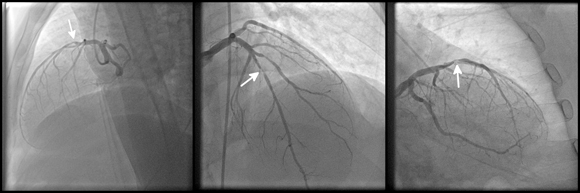

Each additional annotation on the image, other than the biopsy or the medical mage itself – may lead to incorrect training of the algorithm. An diagnostic image of coronary heart disease | kalewa, Shutterstock